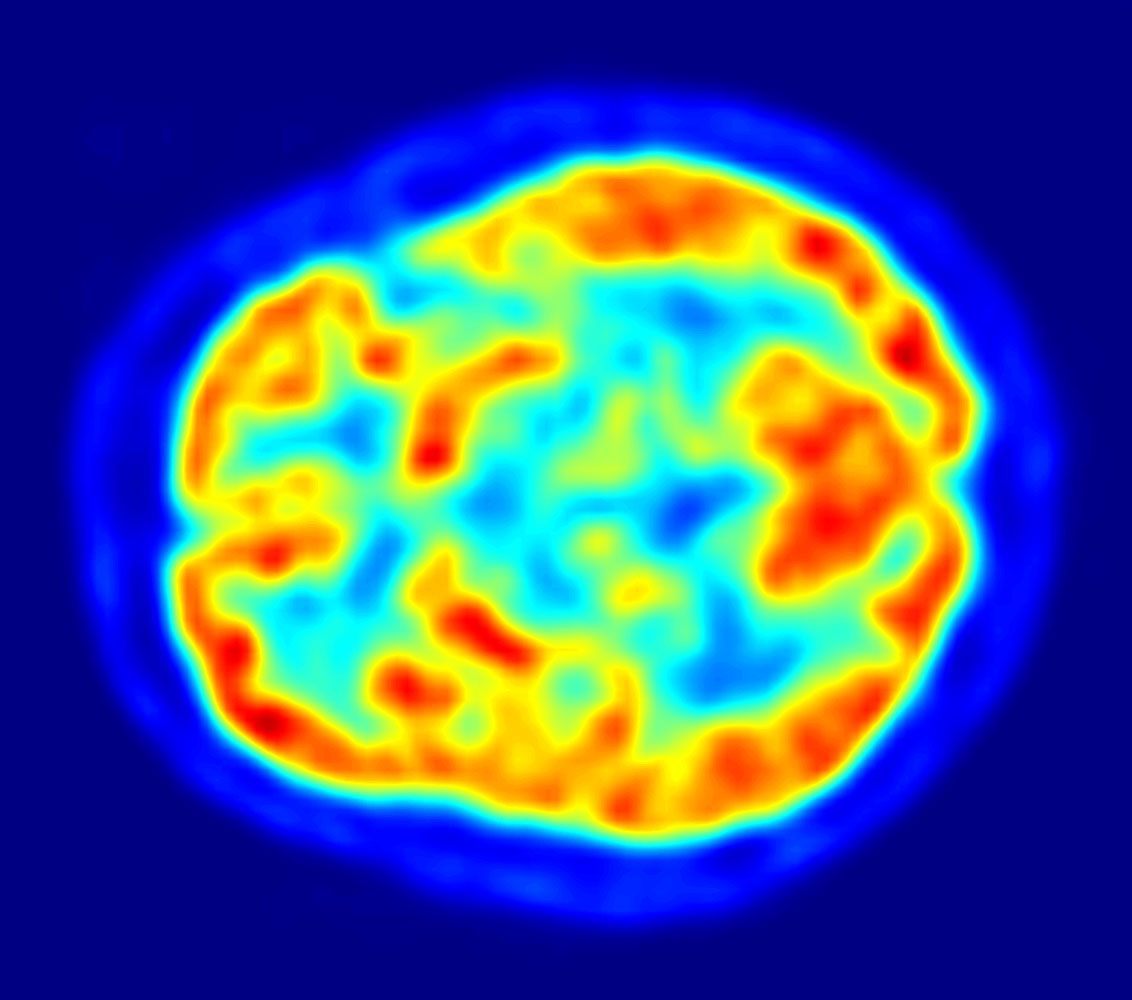

https://cdn.steemitimages.com/DQmXhXjaCg3mCUfsnXeuiGFT9x91R2FzYQxoRRAQPVWzXEj/Img-5-PET-image.jpg

A Transaxial slice of PET scan of the Human Brain

Image Source:wikipedia liscence: public domain

Positron Emitting Tomography (PET) is an imaging procedure that involves the detection of signals produced by the annihilation of a positron and an electron yielding two photons of 511KeV travelling in opposite directions. Unlike the early nuclear procedures that emit gamma rays, PET makes use of isotopes that decay to emit positrons (a negatively charged electron). A deeper attention was paid to the use of short-lived isotopes because the majority of life-sustaining metabolic processes occurs within a very short period of time. However, cyclotrons are designed with flexibility to produce isotopes with half-life short enough to trace metabolic pathways. At first, PET makes use of the detection of annihilation radiation over a single photon but within a short period, there was advancement from the single photon technique to a double photon technique. The double photon technique makes use of 511 KeV photons moving in opposite direction and in coincidence with reference to the source of action thereby creating a more defined image. The development of positron cameras also improves the sensitivity and resolution of the PET. In the early 1970s, computer technology was introduced to the field of medical imaging and this led to the advent of Computer Tomography (CT scanning). CT was a momentous advancement in imaging technology as it allows multiple tomographic images to be obtained digitally. Before the advent of CT, X-ray images were taken on plane films which could only show the position and displacement of tissues (especially bones). However, CT allows the X-ray tube to be rotated at different angles around the area of interest and the detectors pick up the measure of penetration as the radiation passes through the body tissues.